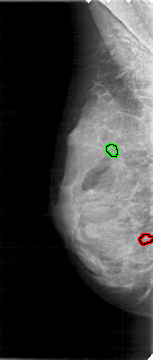

A_1721_1.RIGHT_CC

RIGHT_CC LINES 4456 PIXELS_PER_LINE 2086 BITS_PER_PIXEL 12 RESOLUTION 43.5 NON_OVERLAY